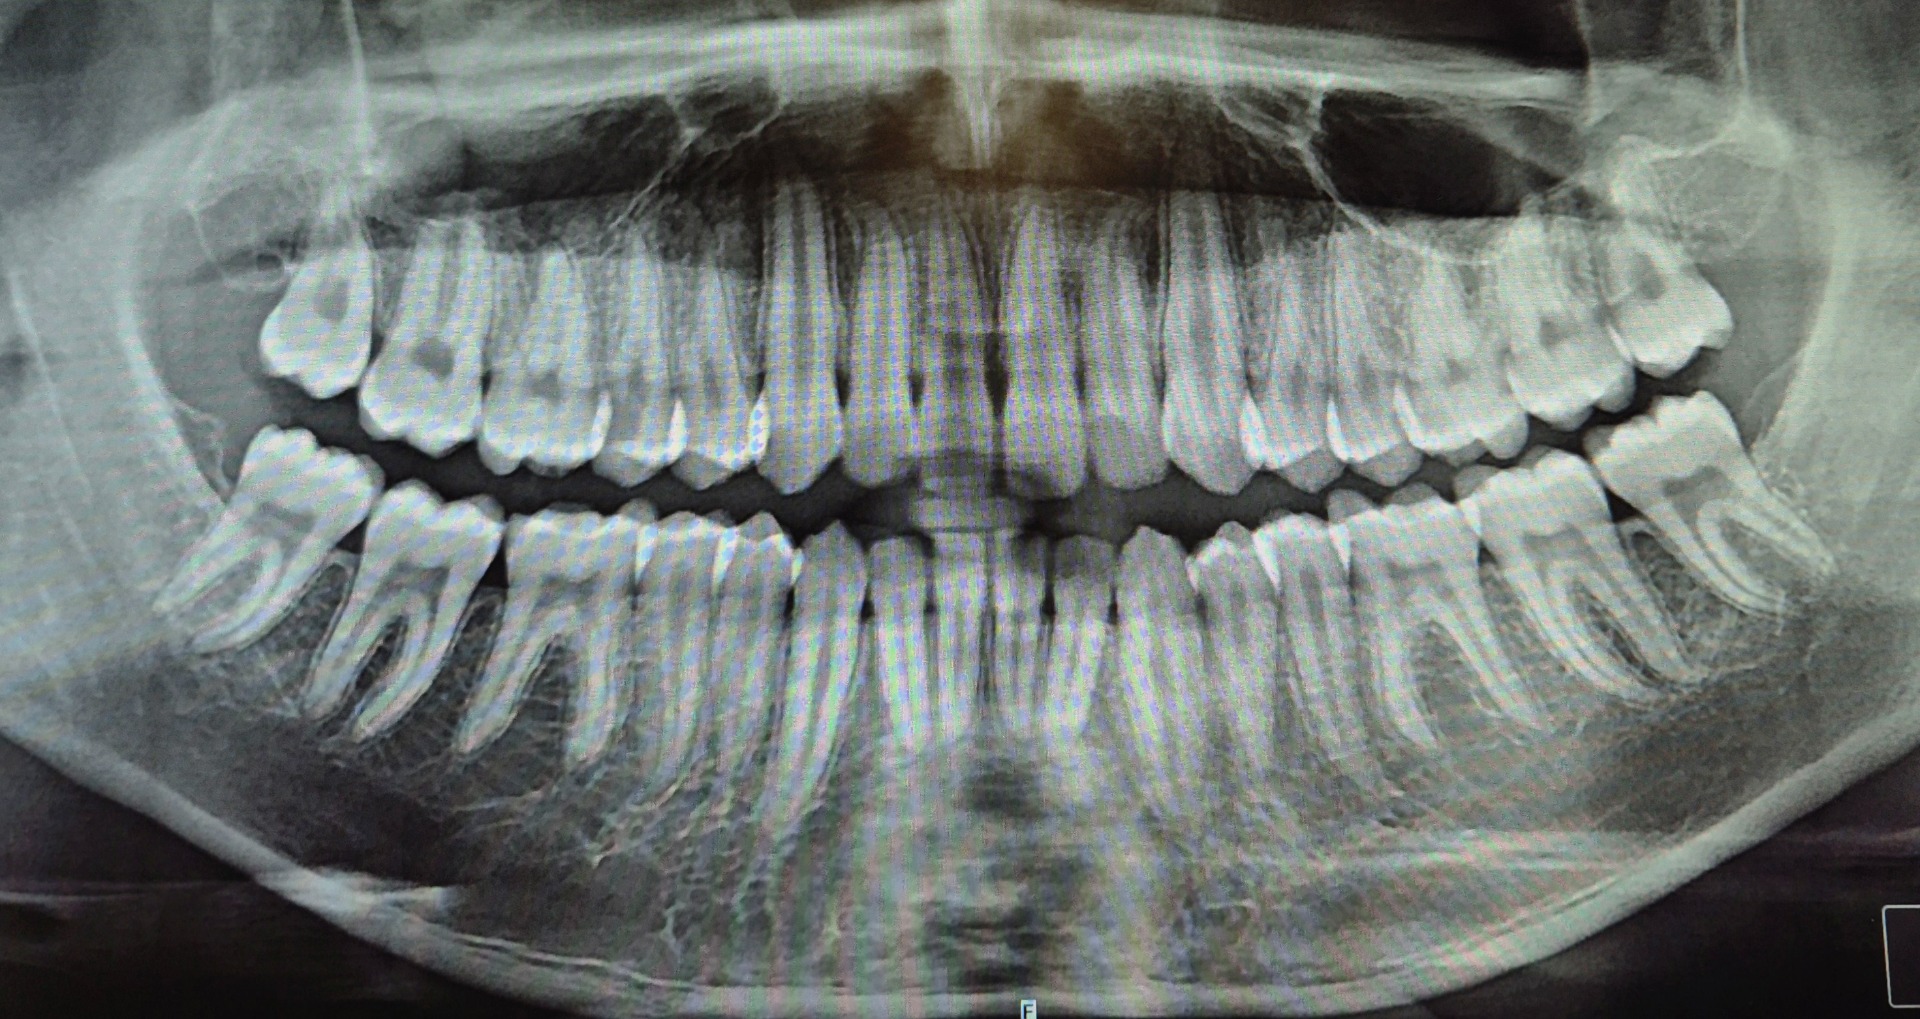

Góckutatás,teljes körű állapotfelmérés panoráma röntgen készítésével.